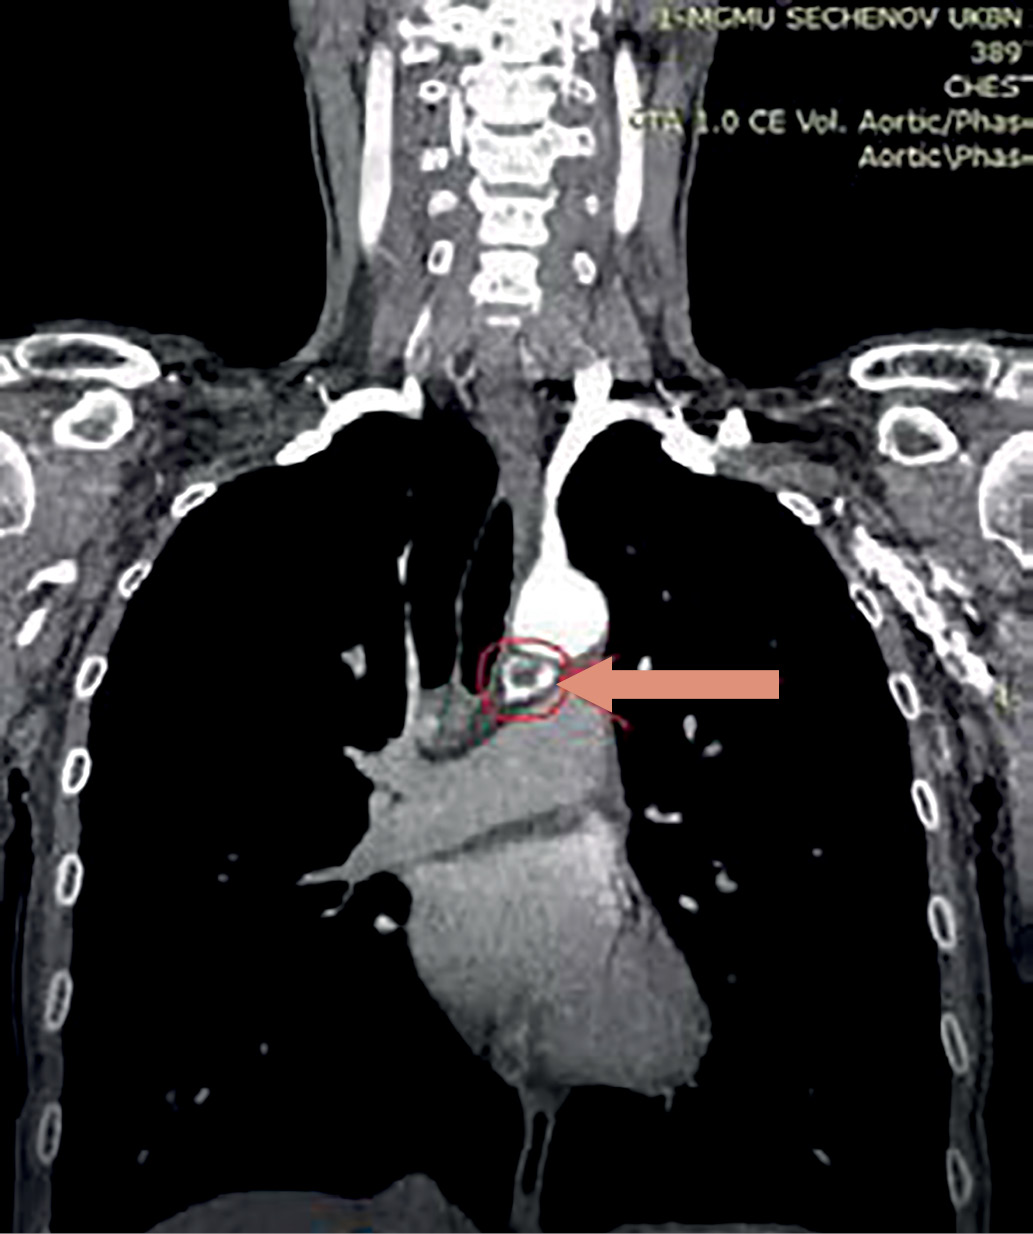

6. Рисунок 6. Томограмма, фронтальная проекция. Новообразование ОЩЖ указано стрелкой. | |